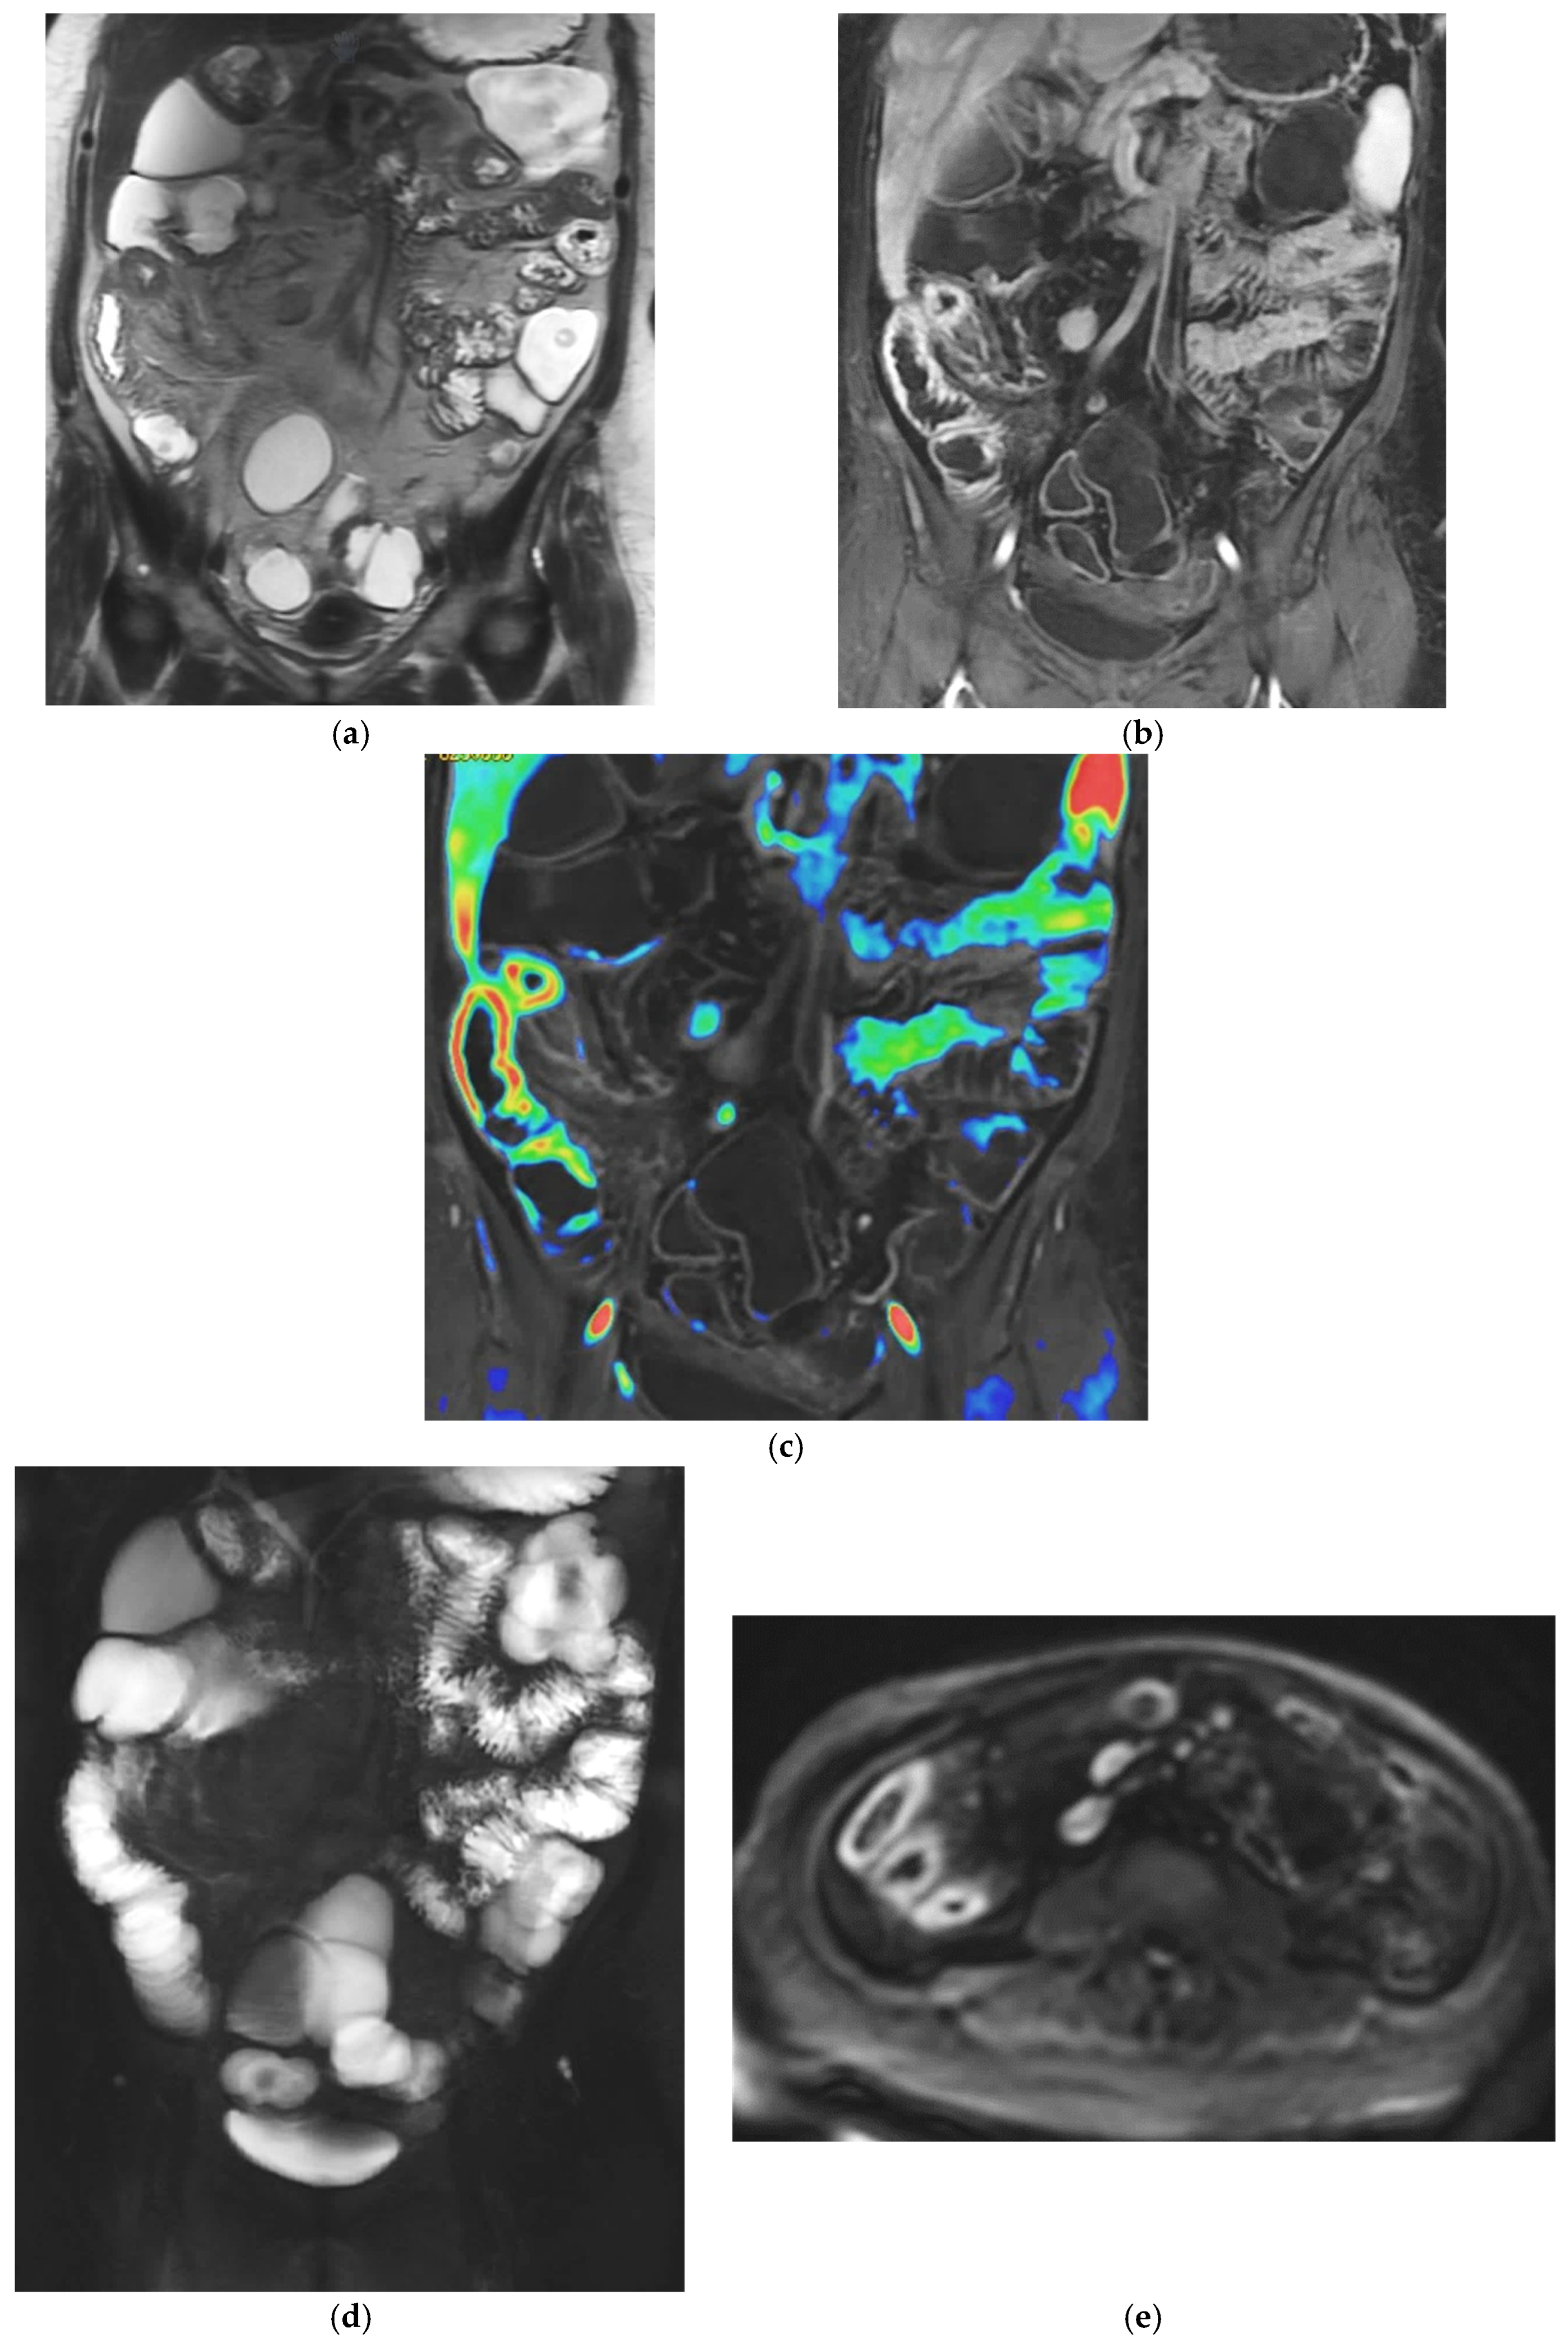

T2-weighted sequences (Figure 1a–c) are fundamental for a comprehensive morphological assessment of Crohn’s disease on both axial and coronal planes. They allow accurate definition of disease location, longitudinal extent, and severity, including evaluation of bowel wall thickening, luminal narrowing, and the presence of penetrating complications such as fistulas and abscesses at any level of the small and large bowel. These sequences are also essential for assessing extraintestinal manifestations of disease, including inflammatory changes of the surrounding mesenteric fat. Beyond structural assessment, T2-weighted imaging plays a pivotal role in the detection of inflammatory activity through the identification of mural and mesenteric oedema. In particular, Fat-Suppressed T2-weighted sequences enhance the conspicuity of oedematous tissue with a higher T2-signal, and currently represent the only imaging technique capable of directly demonstrating oedema at the level of the intestinal wall, mesenteric lymph nodes, and mesentery. Oedema is the hallmark of active inflammation, reflecting increased vascular permeability and interstitial fluid accumulation [6,12,13,14,15,16]. As such, it provides information that is complementary to mural hypervascularization observed on contrast-enhanced sequences, contributing to a more integrated and comprehensive assessment of disease activity [15,16]. Pre- and post-gadolinium–enhanced T1-weighted sequences enable detailed assessment of mucosal and transmural enhancement patterns (Figure 1d–g), which reflect bowel wall vascularity and the degree of inflammatory activity. These sequences are essential for evaluating not only the affected bowel segments, but also associated inflammatory changes in the mesentery and regional lymph nodes.

Figure 1.

20-year-old female patient with typical Crohn’s disease of the terminal ileum, evaluated with a 3T Magnet, following oral ingestion of 1500 cc of PEG solution. (a): Coronal T2w images obtained with breath-hold acquisitions show diffuse inflammatory thickening of the last ileal loop exceeding 15 cm in length. Note how the remaining loops of the small bowel wall appear normal in contrast with the affected ileal loop. (b,c): axial T2 w images showing pathological thickening of the last ileal loop. (d,e): coronal T1-weighted scan after gadolinium injection, showing marked enhancement of the ileocecal valve and terminal ileum wall. In particular, an increased mucosa enhancement is clearly visible in the terminal ileum, well distinguishable from the normal mucosa of the remaining ileal and jejunal loops. The terminal ileum is affected for at least 15–20 cm; local mesenteric hyperaemia is also observed. The entire small bowel is fully displayed (d), including jejunal and ileal loops, which appear normal with respect to the affected terminal ileum. (f,g): Axial Gd-enhanced T1-weighted images show marked concentric wall thickening and enhancement of the terminal ileum with associated mesenteric hyperaemia, due to severe inflammatory involvement. (h): Post-processing “fusion” image, in which the T2 image is merged with the post-contrast T1 image, highlighting the pathological ileal loop in 20-year-old female patient with Crohn’s disease.

This combination of structural and functional information makes MRE particularly powerful in assessing CD inflammatory activity. Increased mural thickness, hyperintensity on T2-weighted imaging, layered or transmural enhancement after contrast administration and restricted diffusion are features that correlate closely with endoscopic markers of disease severity [6,7,8,9,10,11,12,13,14,15,16,17,18,19,20]. Indeed, these imaging markers form the basis of validated scores such as the Magnetic Resonance Index of Activity (MaRIA), which is now widely accepted as a reliable surrogate for mucosal inflammation in both the ileum and colon [11,12,13,17,19,20,21]. CD activity MRI features can be further enhanced using Fusion Imaging and post-processing techniques, which can synthesize and highlight Gd-enhancement, T2-weighted and DWI at the level of the affected bowel loops (Figure 1h and Figure 2c).

Figure 2.

47-year-old female patient with recurrent ileal Crohn’s disease following resection. (a) Coronal T2-weighted image demonstrating recurrent ileal Crohn’s disease at the anastomotic site, characterized by marked bowel wall oedema. (b) Corresponding axial T1-weighted image after gadolinium administration showing intense mural hyperenhancement of the affected ileal loop. (c) Post-processed color-coded map derived from the T1-weighted gadolinium-enhanced sequence, with areas of maximal enhancement highlighted in red. (d) Single-shot fast spin-echo sequence with follow-through–like appearance, clearly depicting the lumen of both normal and pathological small-bowel loops. (e) Axial diffusion-weighted imaging (DWI) showing marked diffusion restriction within the diseased ileal segment.